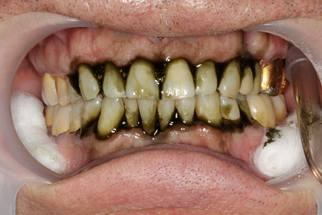

В основной группе 3 проводили фотодинамическую терапию с помощью препарата «Гелеофор» и светодиодного аппарата АФС «Спектр». По сравнению с традиционной антимикробной терапией с применением геля «Метрогил-Дента», противовоспалительный эффект которой наблюдался лишь после завершения всего курса лечения, пациенты группы 3 почувствовали улучшение своего состояния непосредственно на стоматологическом приеме после проведения фотодинамической терапии. После первого сеанса 24,0% пациентов отмечали снижение дискомфорта и болевых ощущений в полости рта, на которые жаловались до лечения. После второго сеанса ФДТ уже 62,0% пациентов субъективное улучшение. После третьего сеанса практически все пациенты (92,0%) отмечали улучшение состояния пародонта, снижение кровоточивости при чистке зубов, уменьшение воспаления десны и болевых ощущений. Улучшение состояния тканей пародонта подтверждалось и при объективном обследовании полости рта (Рисунок 14).

| Клиническая картина до лечения | Ортопантомограмма до лечения |

| Проведена профессиональная гигиена | Обработка ПК гелем «Гелеофор» |

| Активация фотосенсибилизатора | Состояние после первого сеанса ФДТ |

| Состояние после второго сеанса ФДТ | Состояние после третьего сеанса ФДТ |

| Рисунок 14. Динамика состояния тканей пародонта у пациента с ХГП тяжелой степени группы 3 в ходе проведения курса фотодинамической терапии. | |